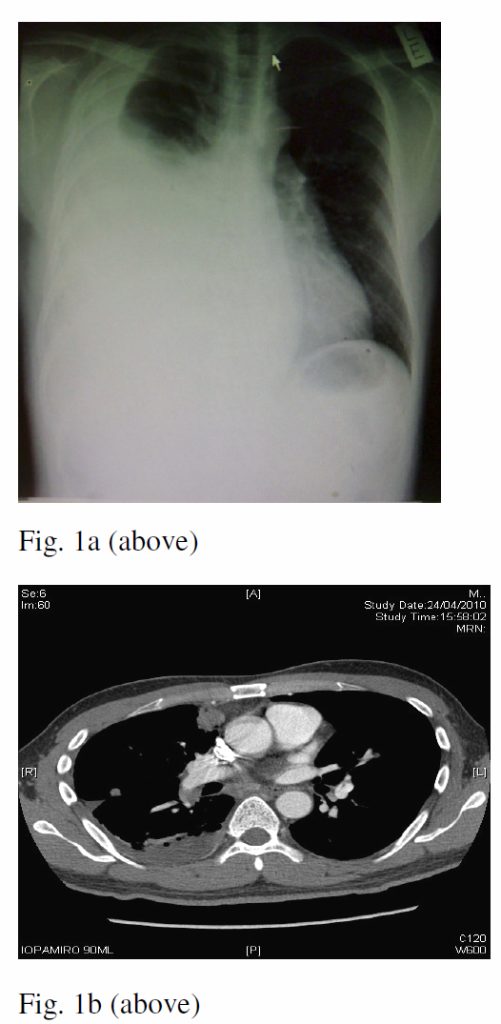

The patient was a 36 year-old non-smoker with no family history of lung cancer, complained of insidious onset of breathlessness and dry cough for weeks. Physical examination showed right pleural effusion. His CT thorax showed an enhanced soft tissue lesion (2.2cm x 1.9cm) at the anterior segment of right upper lobe (Fig. 1a & 1b). There were also another 0.5cm enhancing soft tissue nodule at the lateral segment of right middle lobe, pre-tracheal lymphadenopathy and collapse consolidation of basal segment of right lower lobe. Sputum was not available for investigation. Diagnostic thoracocentesis yielded heavily blood-stained pleural fluid. Closed pleural biopsy was negative but the pleural fluid cytology showed metastatic adenocarcinoma. The final diagnosis was advanced bronchogenic adenocarcinoma.